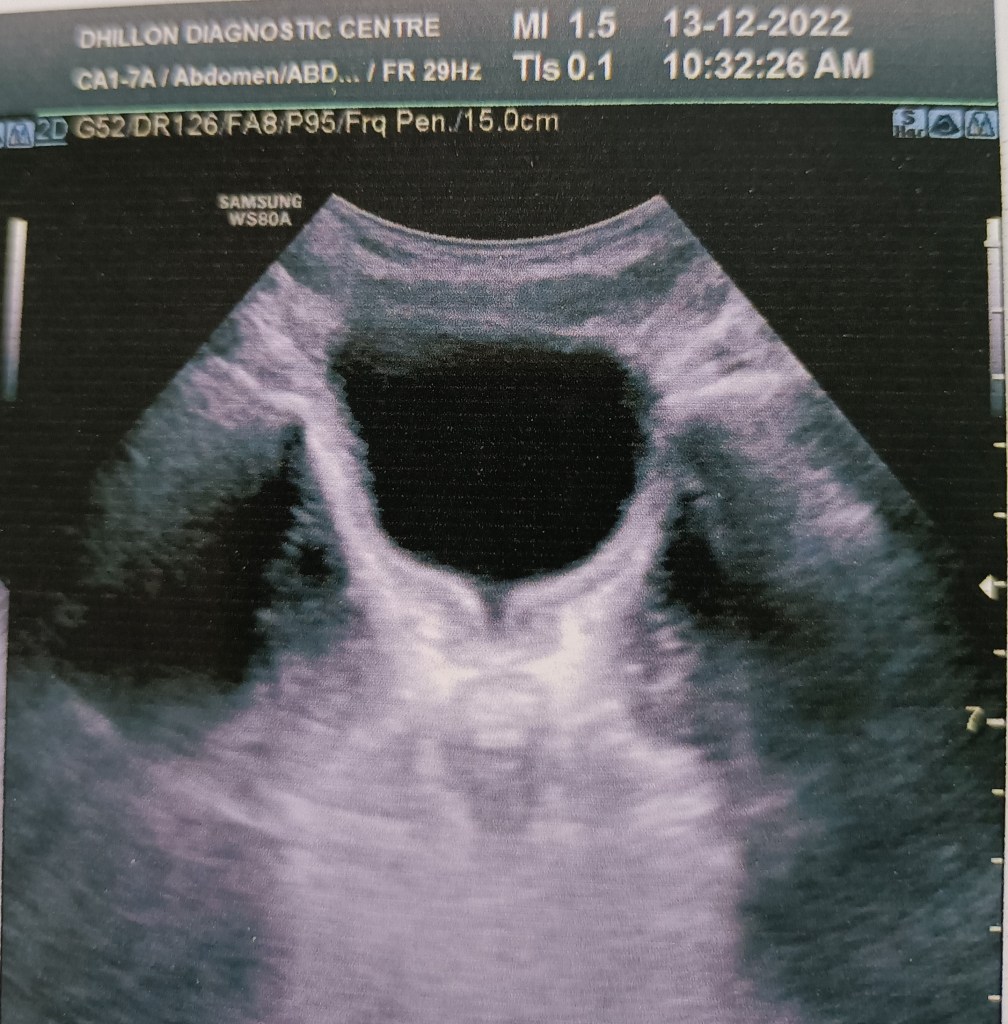

A 13 years old boy presented with acute painful retention of urine at night (it was actually an acute-on-chronic retention, as it came to light later) and since catheterization could not be done due to the tightly stenosed preputial opening, the bladder was emptied with a suprapubic needle. An ultrasound scan in the morning reported circumferential wall thickening of the urinary bladder and a V-shaped deformity of the bladder neck, suggesting a diagnosis of posterior urethral valves.

Paediatric surgical consultation was obtained and an MCU was suggested. This was done and suggested a diagnosis of neurogenic bladder while ruling out posterior urethral valves.

A routine circumcision was performed the same day and the child remains well thereafter.